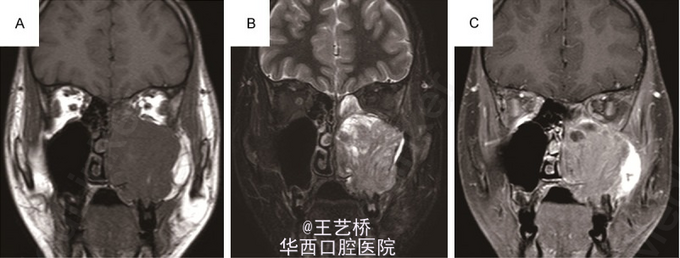

尤文肉瘤是小圆形细胞的低分化的恶性肿瘤,是儿童和青少年第二最常见的恶性骨肿瘤(仅次于骨肉瘤),在头颈部比较罕见,发生在上颌窦则更加少见了。病例中的15岁小男孩出现左侧面部肿胀,实验室检查无异常,进行CT检查时发现上颌窦出现密度影,周围骨质破坏。